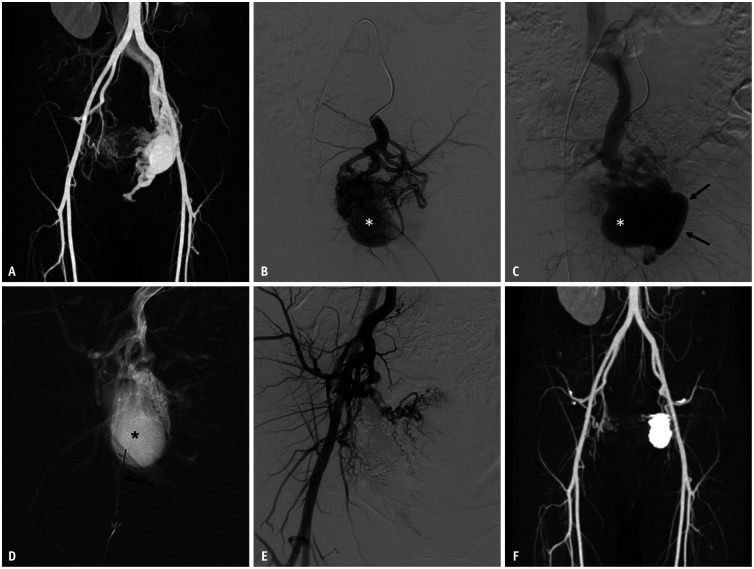

Materials and methods: A retrospective study was performed on 13 patients (median age, 43 years, range 20-62 years, 7 males) who underwent transvenous coil embolization for Type IIa pelvic AVM (characterized by multiple arterioles shunting to focal venous segments of a single draining vein) without the use of additional liquid embolic agents from March 2017 to February 2023. Treatment outcomes were analyzed based on clinical evaluations, post angiography findings, and follow-up CT.

Results: Fourteen procedures were performed on 13 patients. Except in one patient, all treatments were completed in a single session. Transvenous access was employed in 10 procedures, whereas direct puncture was used in four sessions. The embolization procedures used an average of 55.7 ± 58.5 coils (range, 7-238) and lasted an average of 127.3 ± 39.5 minutes. The technical success rate was 92.9% (of 13/14). All patients reported symptom improvement. Follow-up CT scans showed complete occlusion of the AVM without recurrence in ten of the 13 patients. There was one minor adverse event: a small retroperitoneal hemorrhage, likely related to direct puncture, which resolved spontaneously. No other adverse events were observed.